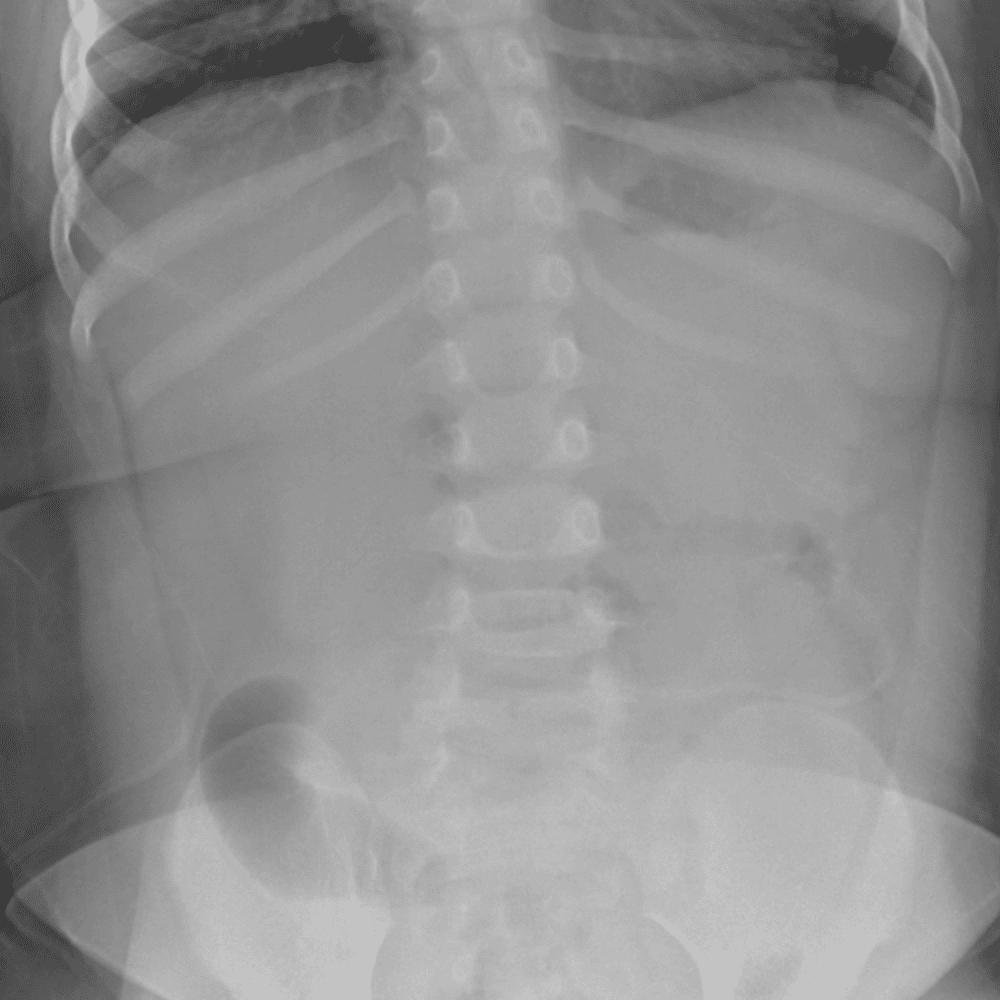

Peds Abdomen

Practice

Simulates call by including subtle or difficult cases and some normals.

30 cases